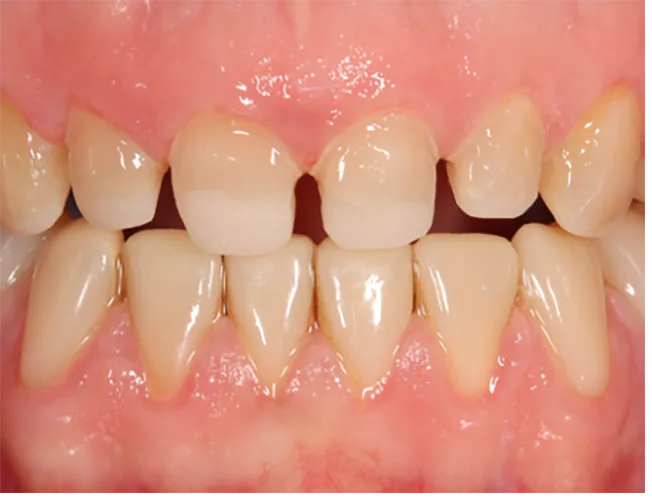

Die additive Fertigung von festsitzendem Zahnersatz kann in zwei weitere Gruppen eingeteilt werden: der provisorische Zahnersatz sowie der definitive Zahnersatz (Abb. 4a und b). Die Anforderungen für permanente Restaurationen sind deutlich höher, was erklärt, weshalb nicht jedes Komposit bzw. Material für definitive festsitzende Restaurationen zugelassen ist.

Die Hauptindikation der additiv gefertigten Restaurationen sind Einzelzahnrestaurationen wie Inlays, Onlays, Veneers, Teilkronen oder Vollkronen (Abb. 5). Aber auch der Einsatz als kurzspannige Brücke (provisorisch oder definitiv) ist möglich (Abb. 6). Der Einsatz additiv hergestellter Non-Prep-Langzeitprovisorien stellt eine außerordentliche Indikation dar und wird von den Herstellern nicht aufgeführt (Abb. 7).